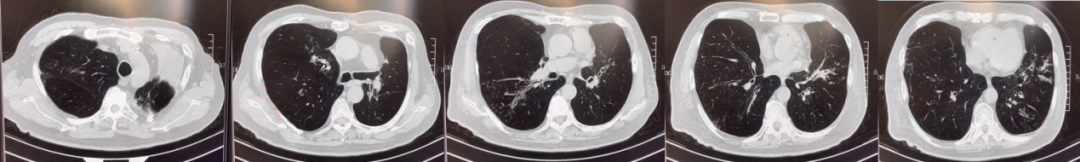

abp在医学是什么意思美例新声病例分享 | 复发活动性变应性支气管肺曲霉病(ABPA)咳嗽患者诊治经验分享_https://www.jmylbn.com_新闻资讯_第11张

入院后胸部CT-2021年10月